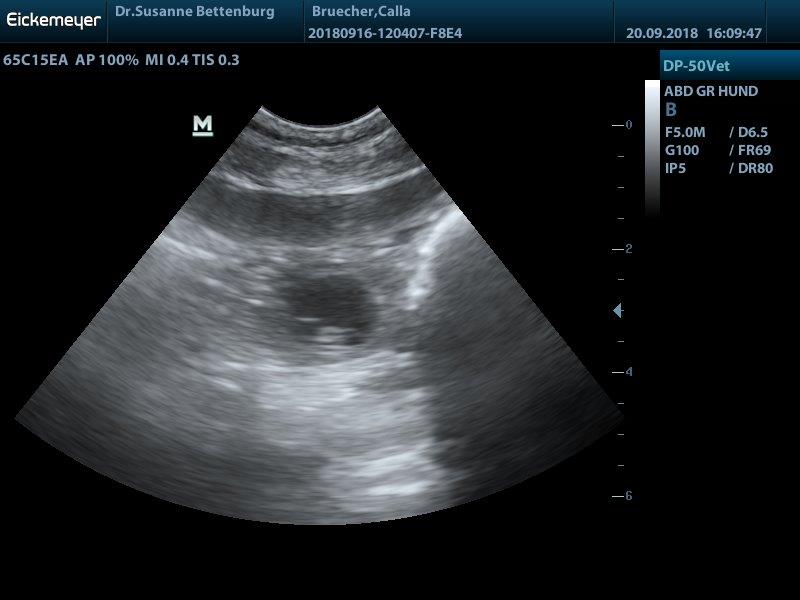

Juhuuu Calla ist trächtig...

wir haben viele kleine Baby's gesehen und erwarten ende Oktober einen normal großen Wurf